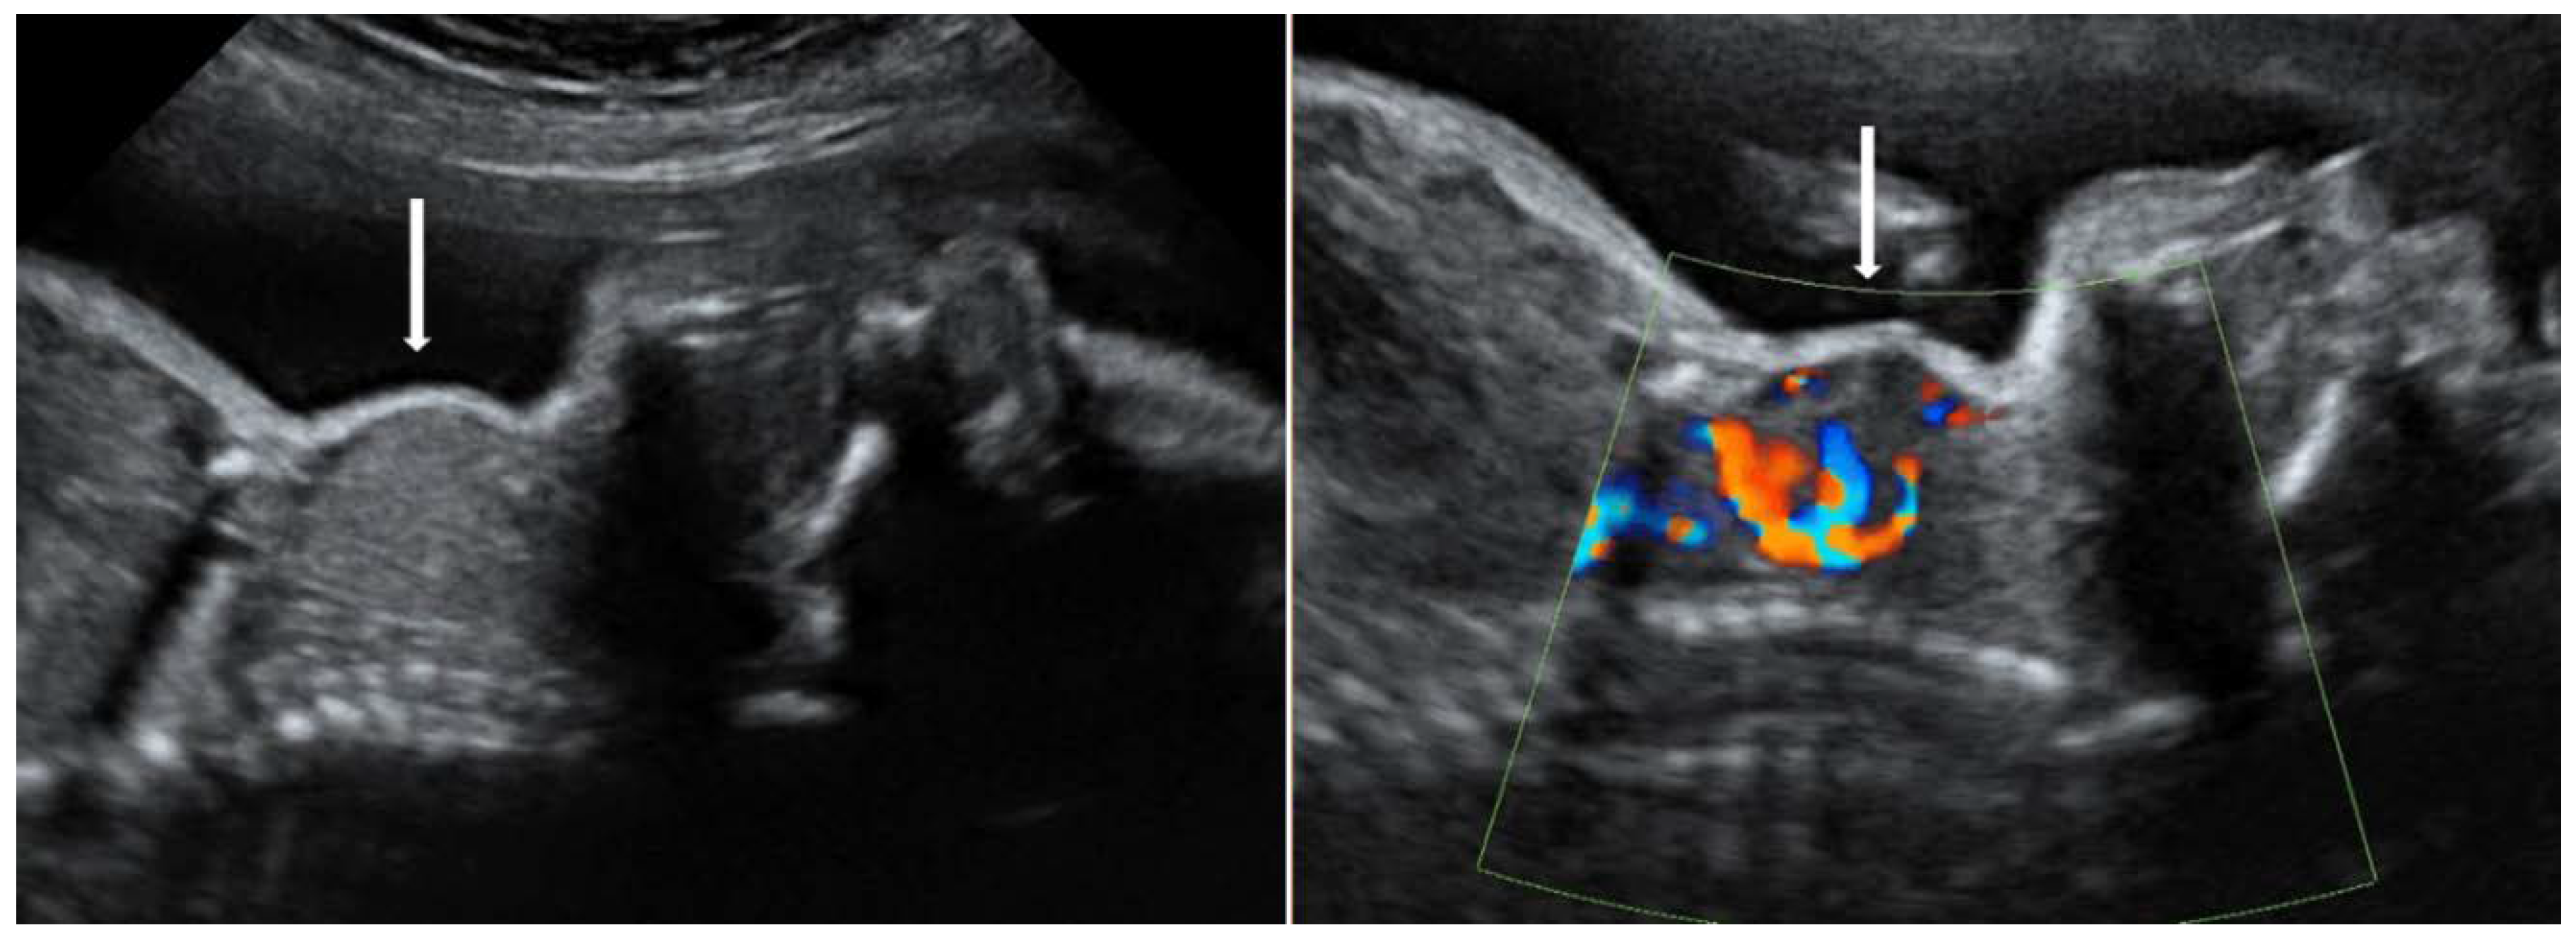

- Huel, C.; Guibourdenche, J.; Vuillard, E.; Ouahba, J.; Piketty, M.; Oury, J.F.; Luton, D. Use of ultrasound to distinguish between fetal hyperthyroidism and hypothyroidism on discovery of a goiter. Ultrasound Obstet. Gynecol. 2009, 33, 412–420. [Google Scholar] [CrossRef] [PubMed]

- Panaitescu, A.; Nicolaides, K. Fetal Goitre in Maternal Graves’ Disease. Acta Endocrinol. (Buchar.) 2018, 14, 85–89. [Google Scholar] [CrossRef]